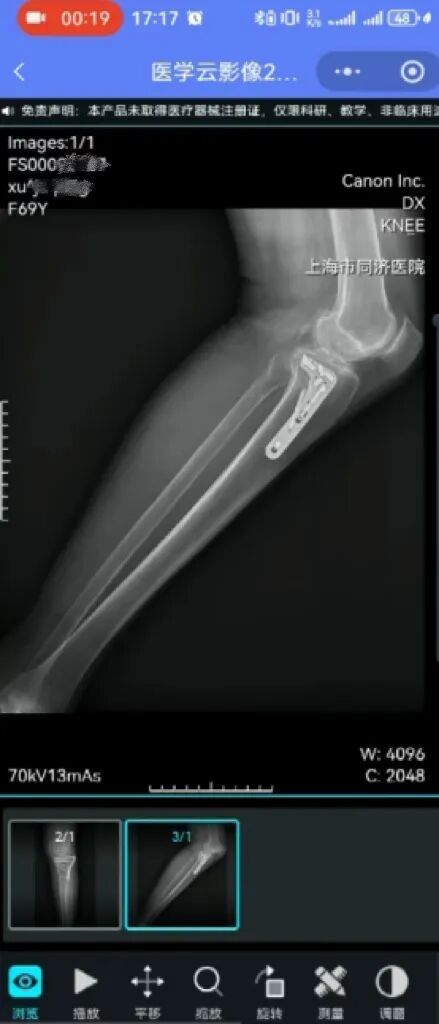

▲(以报告为例,医学云影像可手动调整大小查看病灶细节)

结果出具后即可在线查看,包括详细的影像胶片报告,无需再专程往返医院。